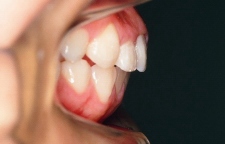

治療前 側面

上顎前歯が出ています